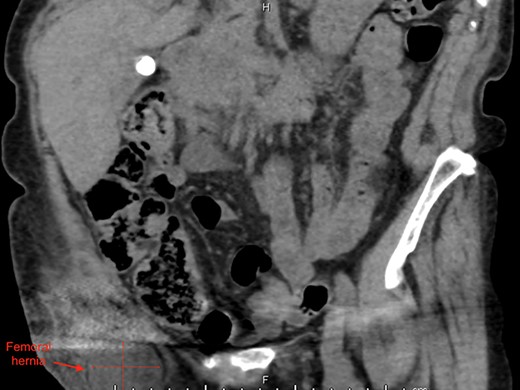

An 87-year-old Caucasian female presented to the emergency department with a 5-day history of worsening right groin pain, with an associated 2-day history of generalized malaise and fatigue. She denied fever, nausea and vomiting or signs of bowel obstruction. Her past medical history included previous right total hip replacement, type 2 diabetes mellitus and chronic renal impairment. Her vitals were normal, and examination revealed a tender right groin lump below the level of the pubic tubercle approximately 4 × 4 cm in size, with overlying erythematous skin changes. Biochemical investigation revealed a normal white cell count of 10.0 × 109/L and neutrophil profile of 7.8 × 109/L but an elevated C-reactive protein (CRP) of 190 mg/L. Contrast-enhanced computed tomography (CT) scan revealed a hypodense rounded lesion measuring 3.8 × 4.3 × 3.1 cm, medial to the right femoral vessels and extending lateral to and below the level of the pubic tubercle in the proximal anterior thigh, most consistent with a incarcerated femoral hernia (Figs. 1–3). The presence of right total hip replacement artifacts precluded accurate assessment for communication of the lesion with the peritoneal cavity.

Imaging modalities also vary in their ability to detect de Garengeot hernias, with MRI being the most sensitive but usually reserved for young pregnant women [9]. Ultrasonography is useful in non-obese patients but is operator-dependent. Hence, CT scan remains the modality of choice as it can at the very least detect a herniating mass projecting below the caecum into the femoral canal with fat stranding [10]. In our case, we relied on CT evidence of possible incarcerated femoral hernia along with a raised CRP of 190 mg/L to influence our decision for surgical intervention.